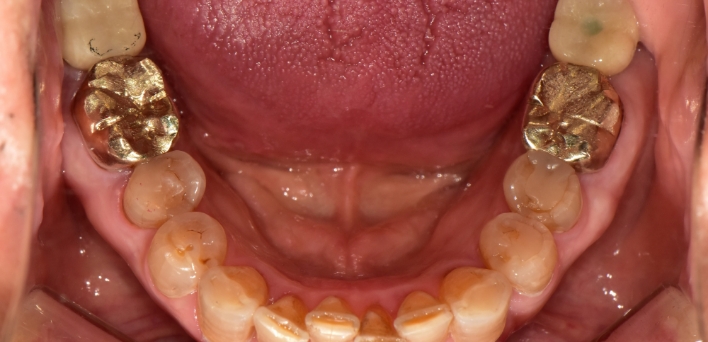

임플란트 케이스

임플란트 Before & After

The seoul dental clinic

※ 더서울치과의원은 의료법을 준수하며 위 케이스는 실제 환자의 동의를 얻은 사례로 치료 전, 후가 동일한 환경에서 촬영되었습니다.

환자 케이스에 따라 부작용이 발생할 수 있습니다. 이 부분은 의료진의 충분한 상담과 체크를 통해 예방하고 줄일 수 있습니다.

[임플란트 부작용] 수술 후 관리가 소홀할 경우 출혈, 주위염 등의 부작용이 발생할 수 있어 구강 위생을 철저히 유지하고, 정기적인 검진을 통해 상태를 점검하는 것이 중요합니다.